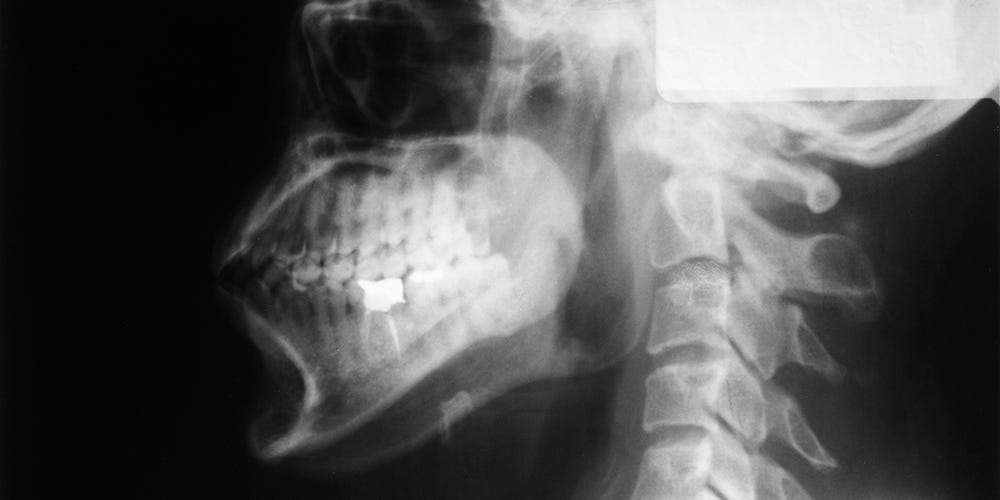

First, he recommended a less invasive test called a barium swallow study, or esophagram—a radiographic exam in which a series of x-rays are taken of the upper gastrointestinal tract while you consume both liquid and pill form of barium sulfate, which highlights the pipe. While the liquid went down without any obstruction during the test, the x-ray technicians did see the barium pill get stuck about halfway down. They had me take three big gulps of water before it finally passed through.